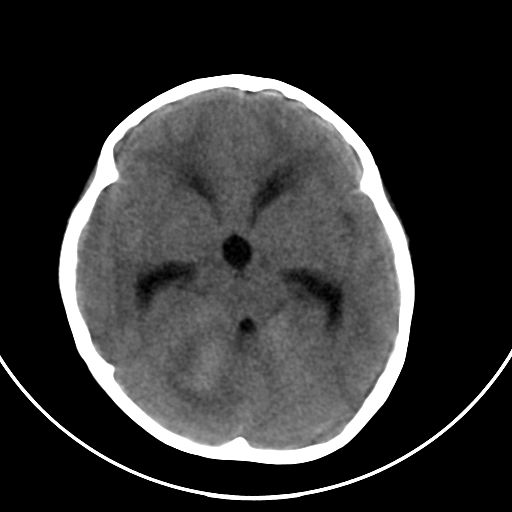

以下是引用zjzjr在2008-7-27 9:56:00的发言:[br]考虑髓母细胞瘤伴梗阻性脑积水.建议增强或mri

以下是引用子十在2008-7-27 9:53:00的发言:[br]考虑髓母细胞瘤